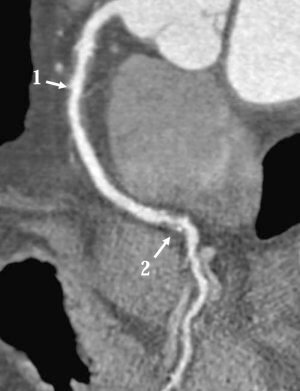

Атеросклероз коронарних артерій

Аортою називається один із самих великих кровоносних судин, який бере свій початок з лівого шлуночка серця, потім розділяється на два основних найбільш відгалуження великих і безліч дрібних. Верхнє відгалуження носить назву грудної аорти, а нижнє – черевна аорта. Ці відгалуження і є коронарні артерії, діяльність яких безпосередньо пов’язана з працездатністю серця, а також органів, розташованих в грудній та черевній порожнині організму.

У більшості випадків виникнення атеросклерозу аорти даний посудину піддається патологічного ураження не повністю, а лише частково, невеликими ділянками. Від місця локалізації патології в аорті залежить і розвиток симптоматичного прояви захворювання. Тому атеросклероз може проявляти себе різними симптомами. Атеросклероз дуже часто стає причиною появи інфарктів, інсультів головного мозку та інших не менш серйозних патологічних процесів.